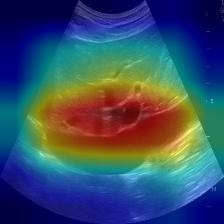

Most deep neural networks (DNNs) based ultrasound (US) medical image analysis models use pretrained backbones (e.g., ImageNet) for better model generalization. However, the domain gap between natural and medical images causes an inevitable performance bottleneck. To alleviate this problem, an US dataset named US-4 is constructed for direct pretraining on the same domain. It contains over 23,000 images from four US video sub-datasets. To learn robust features from US-4, we propose an US semi-supervised contrastive learning method, named USCL, for pretraining. In order to avoid high similarities between negative pairs as well as mine abundant visual features from limited US videos, USCL adopts a sample pair generation method to enrich the feature involved in a single step of contrastive optimization. Extensive experiments on several downstream tasks show the superiority of USCL pretraining against ImageNet pretraining and other state-of-the-art (SOTA) pretraining approaches. In particular, USCL pretrained backbone achieves fine-tuning accuracy of over 94% on POCUS dataset, which is 10% higher than 84% of the ImageNet pretrained model. The source codes of this work are available at https://github.com/983632847/USCL.